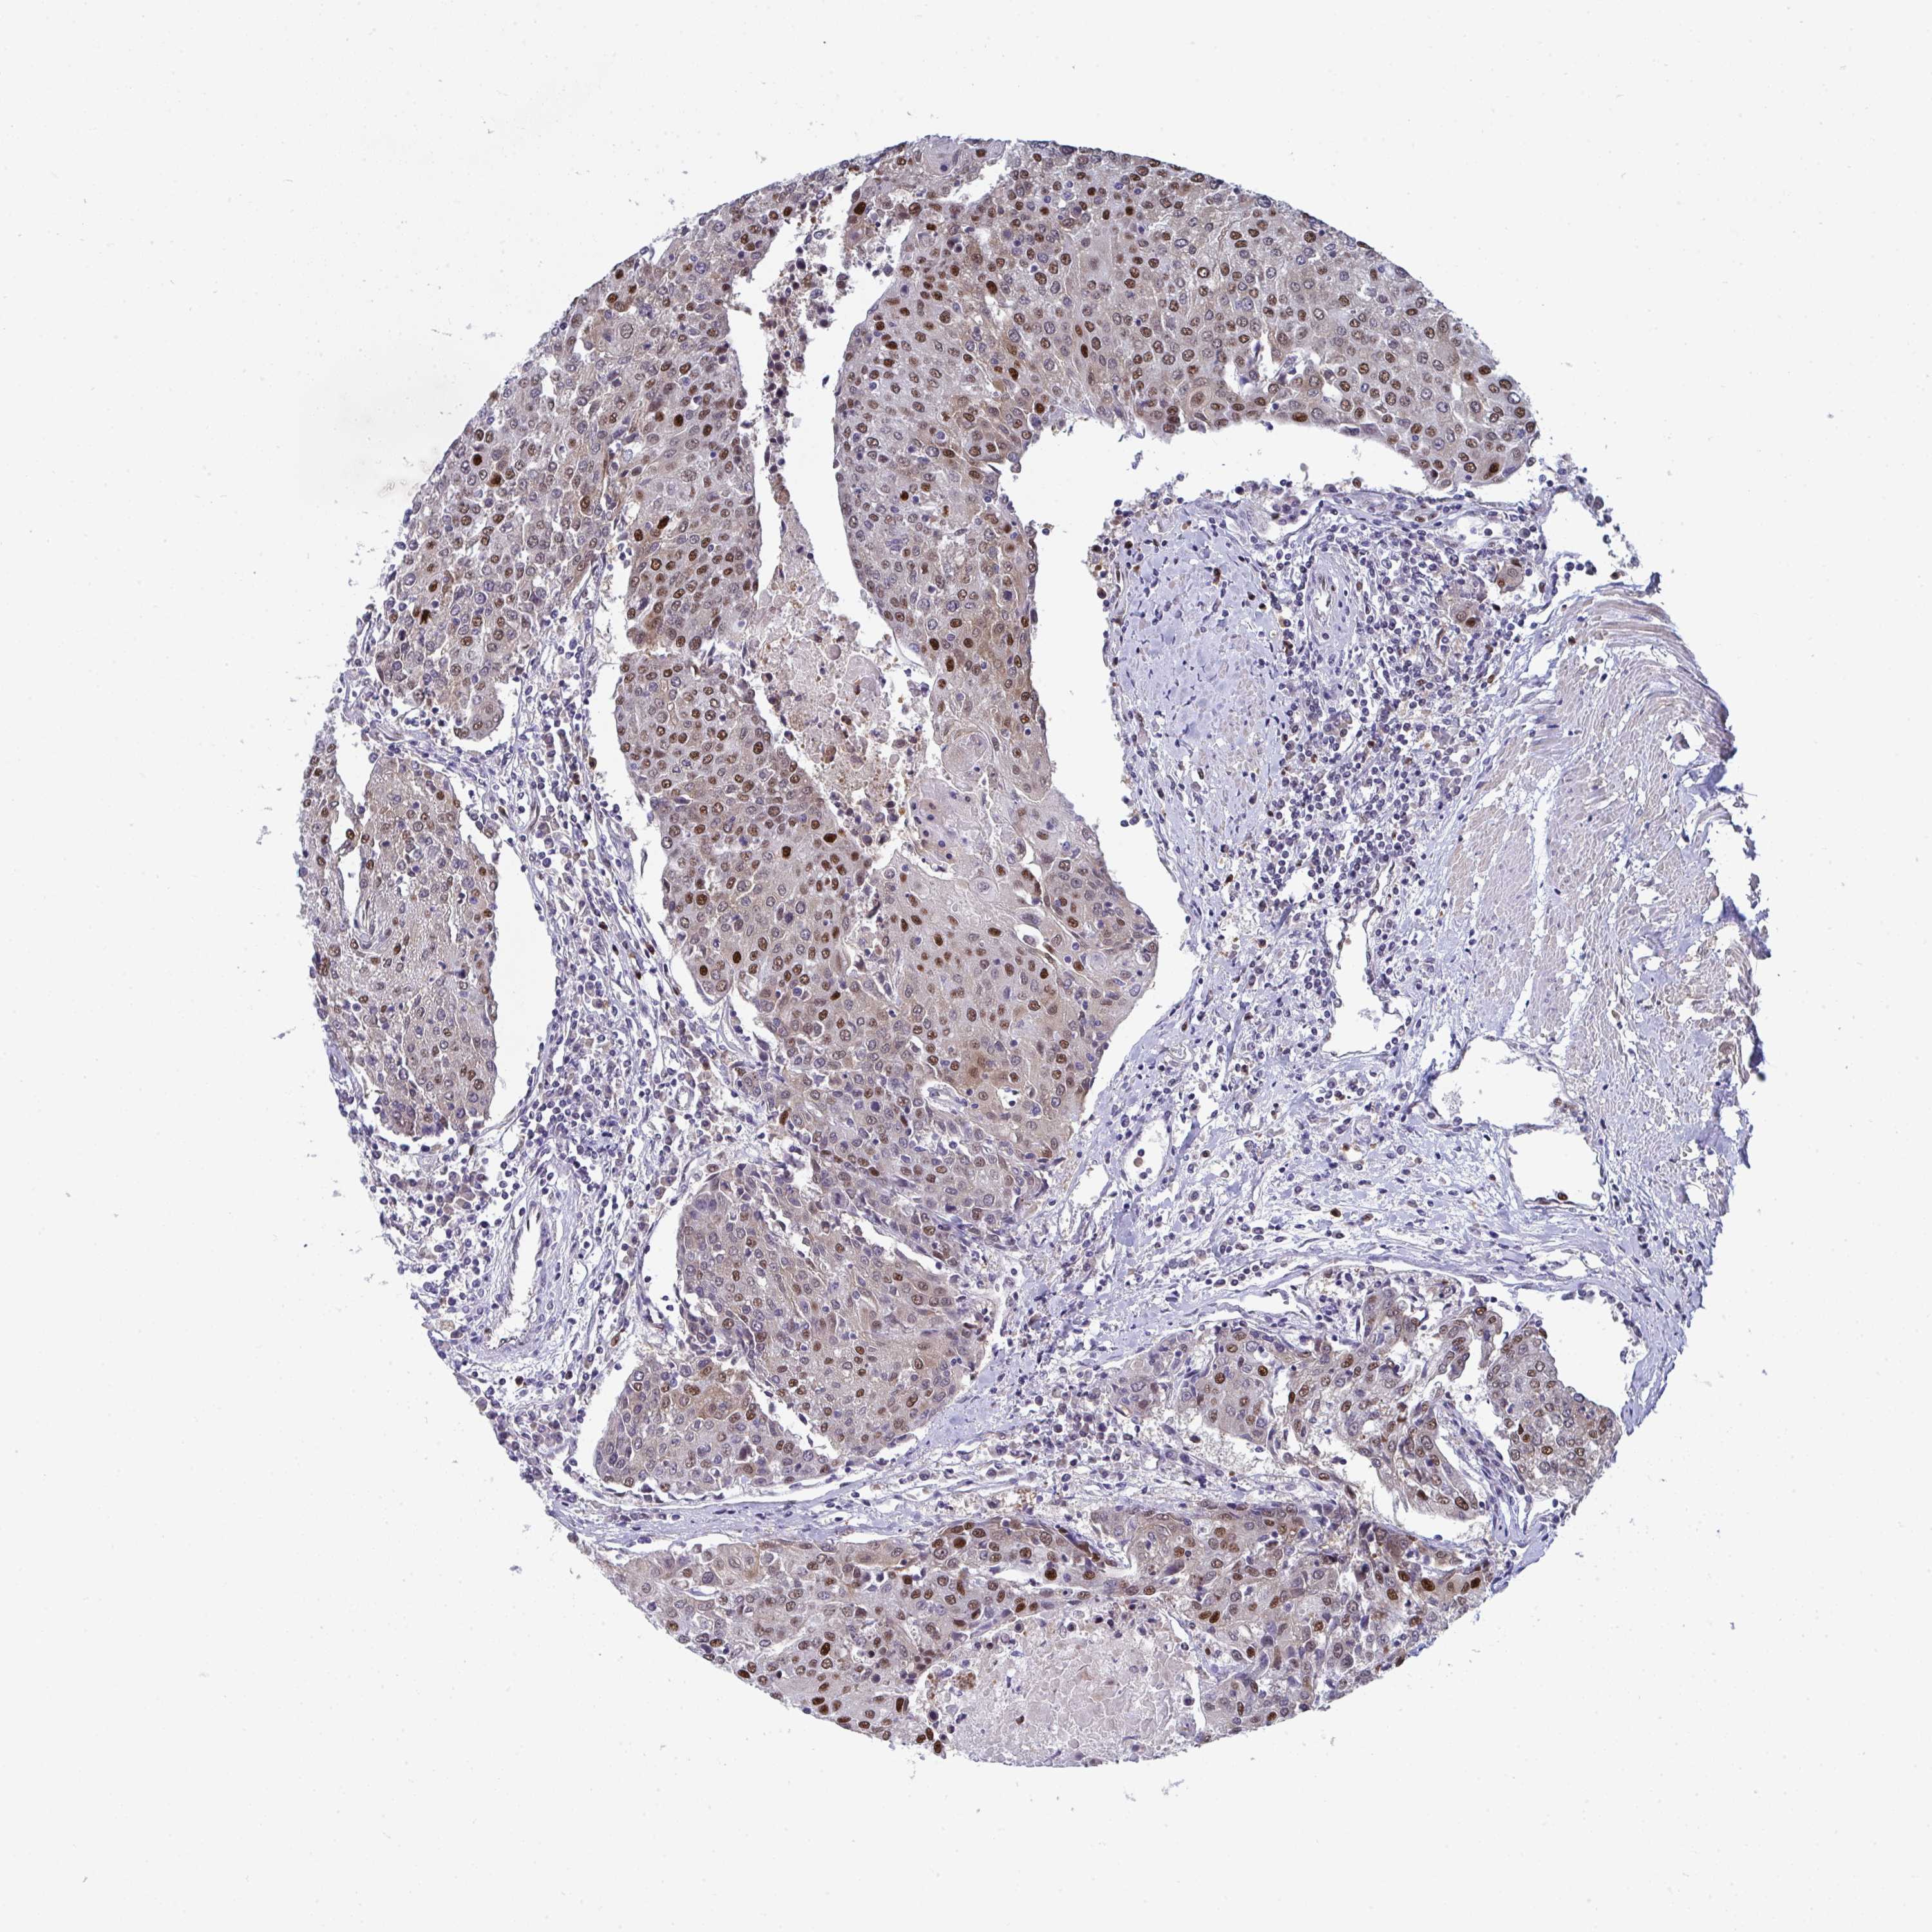

UROTHELIAL CANCER - Protein expressioni

A mouse-over function shows sample information and annotation data. Click on an image to view it in a full screen mode. Samples can be filtered based on level of antibody staining by selecting one or several of the following categories: high, medium, low and not detected. The assay and annotation is described here.

Antibody stainingi

Antibody staining in the annotated cell types in the current human tissue is reported as not detected, low, medium, or high, based on conventional immunohistochemistry profiling in selected tissues. This score is based on the combination of the staining intensity and fraction of stained cells.

Each image is clickable and will lead to virtual microscopy that enables deeper exploration of all samples and also displays staining intensity scores, fraction scores and subcellular localization as well as patient and tissue information for each sample.

Antibody HPA059511

Staining

High

Medium

Low

Not detected

Intensity

Strong

Moderate

Weak

Negative

Quantity

>75%

75%-25%

<25%

None

Location

Nuclear

Cytoplasmic/membranous

Cytoplasmic/membranous,nuclear

Urothelial carcinoma, High grade

Urothelial carcinoma, NOS

Urothelial carcinoma, Low grade